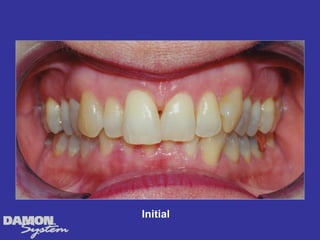

M.J. 14 yrs 6mos Class I severe crowding, deep bite, all Initial cuspids blocked out.